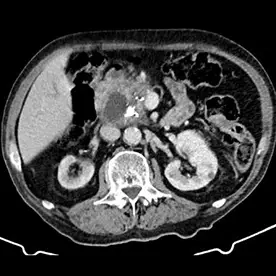

Durchführung einer kontrastmittelgestützten CT-Untersuchung des Abdomens in arterieller und venöser Kontrastmittelphase. Neben einer reizlosen Cholezystholithiasis zeigt sich ein massiv erweiterter D. pancreaticus bis zur Papille und diffuse zystische Pankreasläsionen, teils mit Verkalkungen (Bild 4 und 5) mit dem Hauptbefund im Pankreasschwanz angrenzend an die linke Nebenniere; kein Nachweis solider Anteile (Bild 1). Zusätzlich wurden mehrere kalkdichte Konkremente im Pankreas nachgewiesen, die sich vorwiegend im Bereich des Caput befinden. Keine Lymphadenopathie. Keine metastasensuspekten Herdsetzungen. Als weitere Nebenbefunde wurden eine parenchymverschmälerte Niere rechts und der V.a. auf ein Nebennierenadenom geäußert.

Verdacht auf eine intrapankreatische muzinöse Neoplasie (IPMN) vom Hauptgangtyp. Auch die intra- und extrahepatischen Gallenwege zeigen sich deutlich dilatiert (Bild 2 und 3).